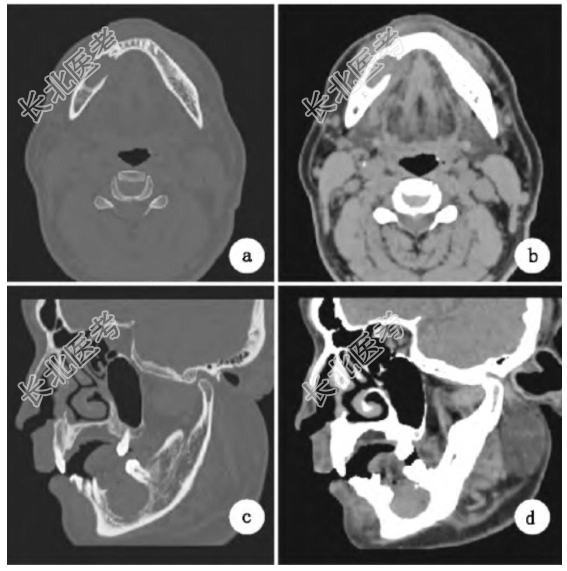

影像学检查:(1)曲面断层示右下颌体后部可见类圆形骨质密度减低影,边界清楚,边缘光滑,大小约3.0cm×2.0cm,牙槽嵴侧骨质局部缺失,向下累及右下颌管上壁,44牙根位于病变内,45、46缺失。(2)螺旋CT层扫(图1)示右下颌体后部病变区域CT值约45Hu,呈软组织密度。